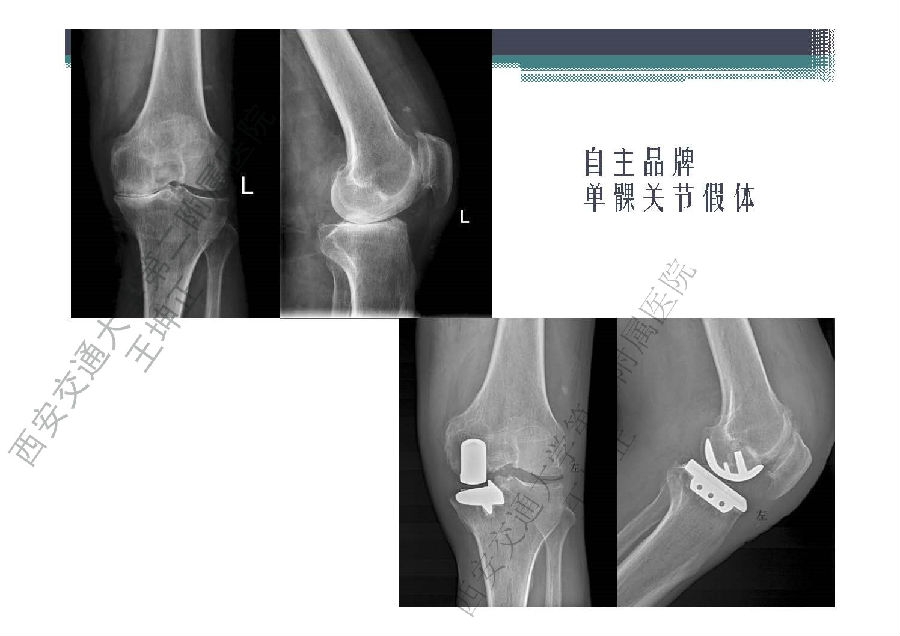

对于关节外科而言快速康复实际上是以病人加速舒适康复为目的,加强围术期的综合管理,包括疼痛和睡眠管理、血栓预防管理、感染预防管理、围术期血液管理,减少放置引流管、尿管、减少止血带应用,减少术后恶心呕吐,尽早进食,尽早康复等,逐步达到无血、无痛、无栓、无感、无肿、无管、无吐、无带等优良效果。为此,小编特邀王坤正教授等多位关节外科的专家参与撰写快速康复外科在关节外科的应用的主题文章,共话“人工关节置换快速康复”新理念,探讨建立符合我国特色的关节置换围手术期管理与快速康复体系,促进我国关节外科技术整体发展与提高。